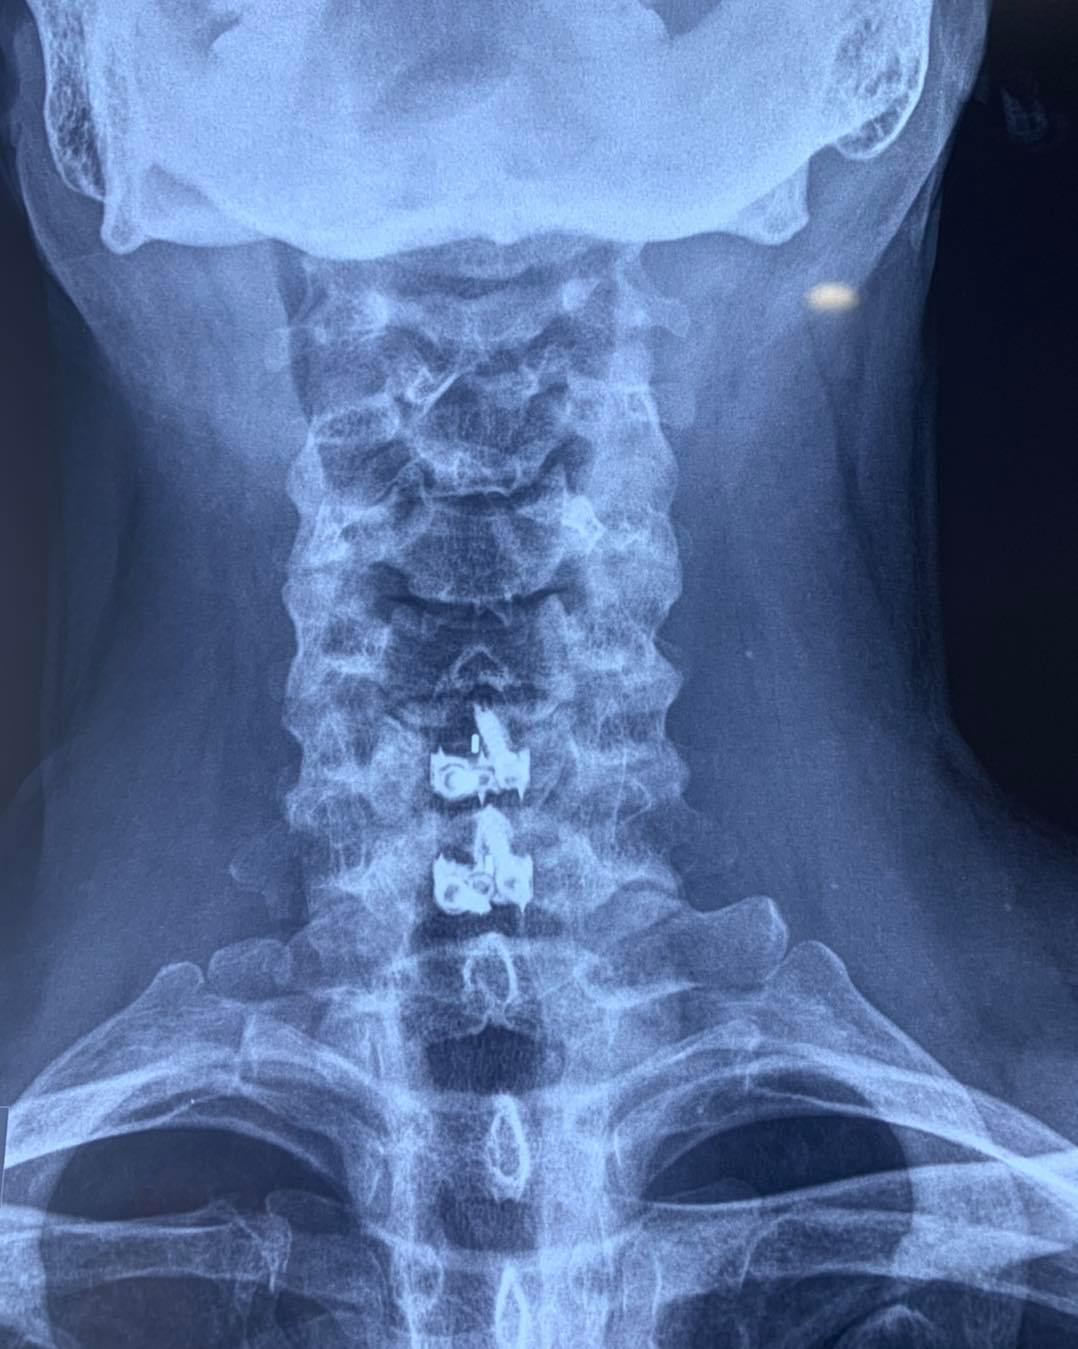

SURGERIES

RESULTS